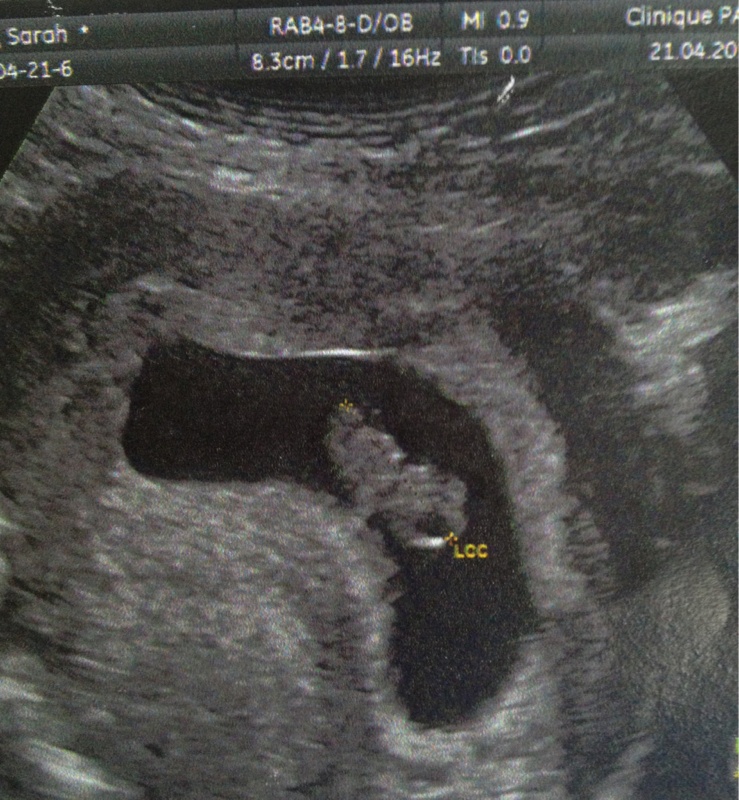

Mon fils n'aime pas les photos donc bon je pourrais pas vous montrer grand chose lol. Voilà son profil et son dos fesses et jambes lol. Mais a L'Echo on a trop bien vu sa bouche son nez des petit pieds ses petites mains fin génial ;)

Moi j'ai une photode ma première echo (quand j'ai su sue j'etais enceinte mais c'est encore tout petit mais c'est tellement mignon , mais il faut que je trouve comment mettre la photo, je suis sur iphone j'ai du mal a trouver lol